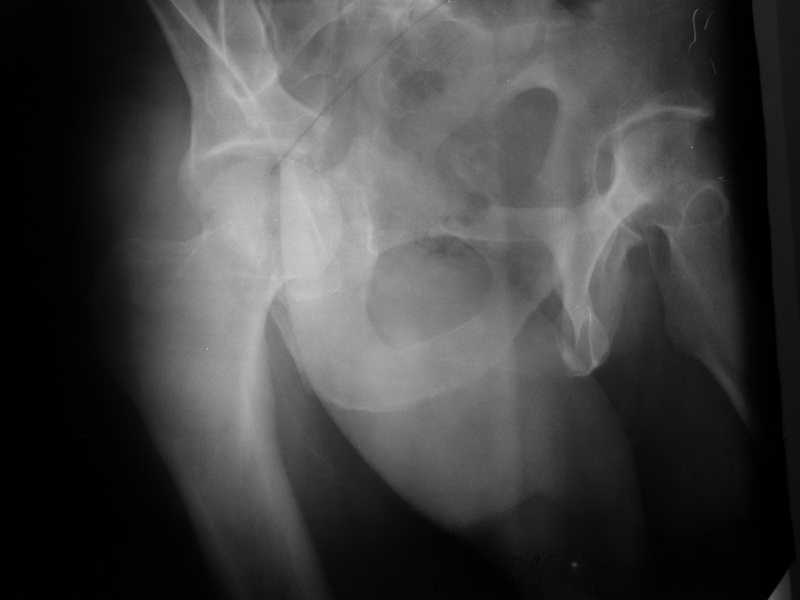

The details of the fracture are not so clear from the images sent...would you be able to send along an AP and Judet images as well as some additional axial images above and below the joint?

I’m not so sure that your patient has a Tr+PW pattern based on the images sent...maybe the fracture’s exact name won’t matter in the long run, but it’d be great to see enough images to make an accurate comment.

Without complete CT images and/or oblique radiographs, it's difficult to answer your question definitively, but it appears that there may not be a posterior wall fracture that requires a posterior approach. A successful reduction through an ilio-inguinal approach will have a faster recovery, and not risk SGN injury or heterotopic ossification.

Here are some more axial images. What is your opinion as for the timing of the operative treatment?